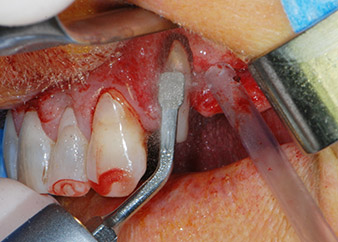

One month later, on the day of surgery, pain and inflammation at tooth 24 were minimal, but mobility of Miller class 2 was still present. After opening the flaps and cleaning the periapical and peri radicular infected tissue, the extent of the bone defect became obvious (Figs. 2 and 3).

At the buccal root, all vestibular and distal bone was missing. Attachment was essentially restricted to the palatal root, underlining the preliminary poor prognosis. Tooth 27 also showed a reduced horizontal attachment and a minimal apical rarefaction (cf. Fig. 1) without clinical symptoms.

total loss of bone and attachment

Fig. 2 and 3: After raising flaps, one month after endodontic revision and initiation of full-mouth periodontal therapy, the buccal root of tooth 24 showed a total loss of bone and attachment.